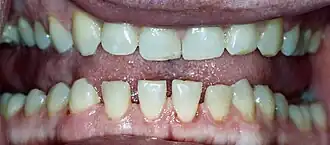

Efeito na formação das arcadas dentárias.